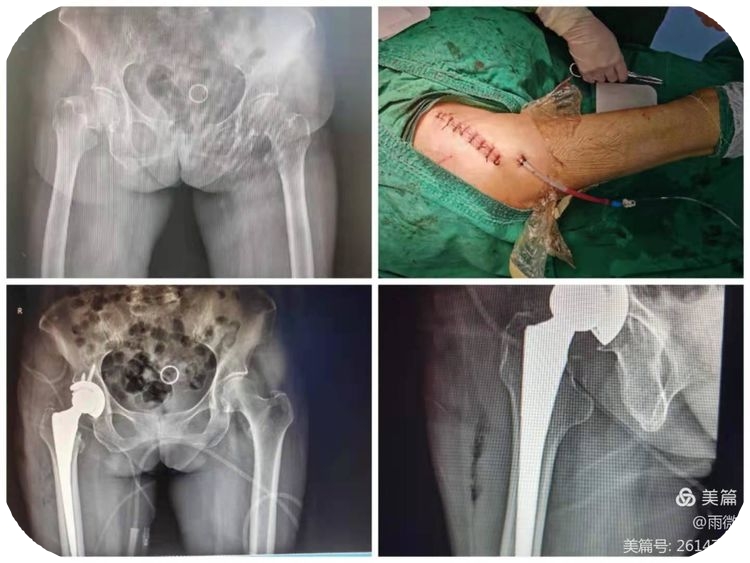

玉林市中西医结合骨科医院创伤二科特长创伤骨折脱位的中西结合治疗,普通手术或微创手术,包括各种关节置换治疗、腰椎疾患、骨质疏松症治疗等。熟练应用快速复位骨折牵引床、G臂、C臂及人工智能机器协助手术。科室有多种物理治疗仪,开展中医中药艾灸治疗等。对指导患者术后快速康复有丰富的临床经验。现有医护人员21名,副高主任医师有1名,主治医生6名。护理人员14名,其中主管护士有3名、护师有2名、护士有9名。